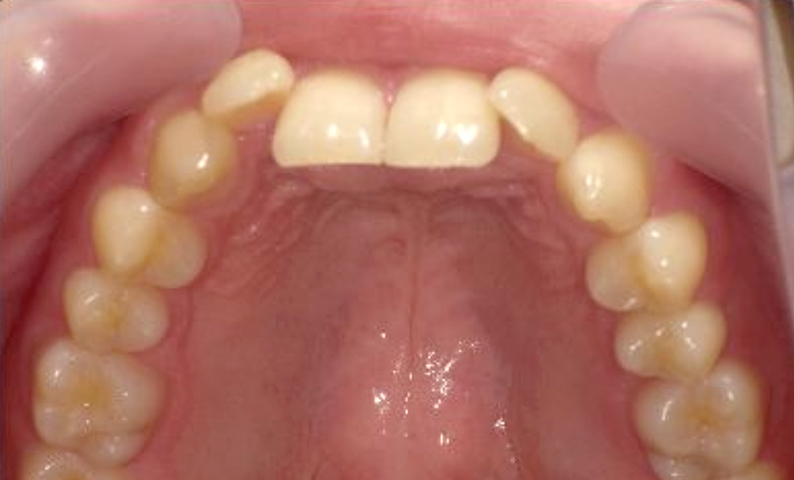

症例_023 上顎だけの部分矯正

治療期間:9ヶ月金額:30万円+税女性前歯のガタガタ上の前歯だけ

| Before | After |